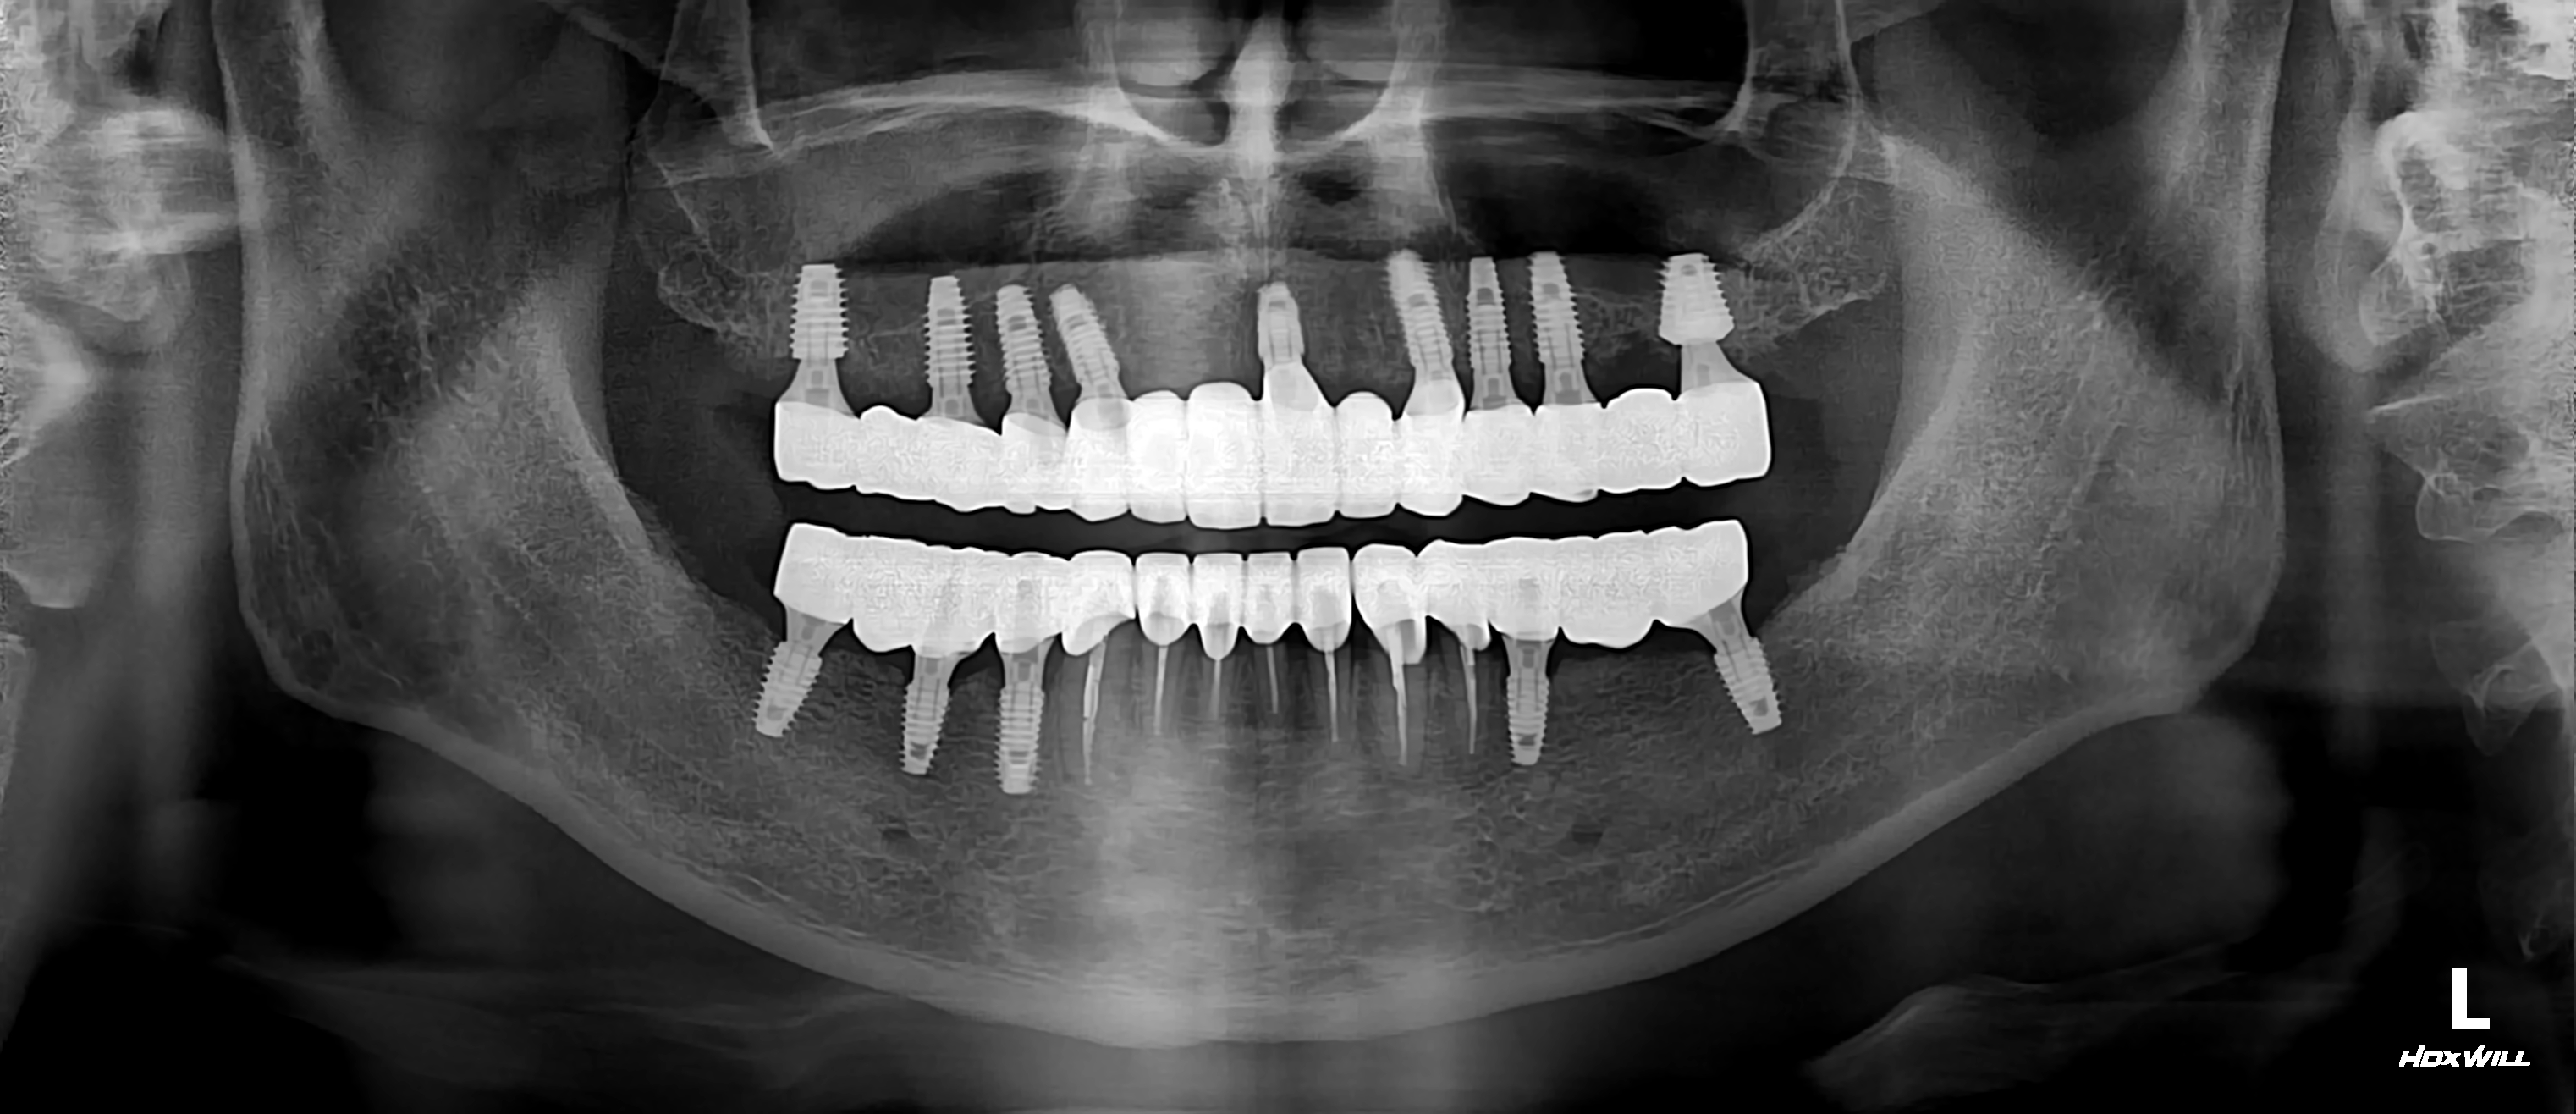

이번에는 50세 남성 중국인 환자분의 케이스를 소개해드립니다.

처음에 오셨을때 구강건강 상태가 매우 심각하셨는데요.

잦은 흡연과 평소 딱딱한 음식을 즐겨드시던 습관때문에 만성적인 치주염과 파절이

꽤 심하게 진행되신 상태였습니다.

치아 상태에 비해 다행히 치조골 상태는 좋으신 편이셔서 임플란트 진행이 생각보다 수월했습니다.

그 결과 치료 진행하신지 약 10개월만에 환한 웃음을 되찾으셨는데요.

하악 전치부 치료는 하지 않고 아래처럼 치료를 마무리 했습니다.

그래서 현재는 이렇게 환한 미소를 찾으셨지요...